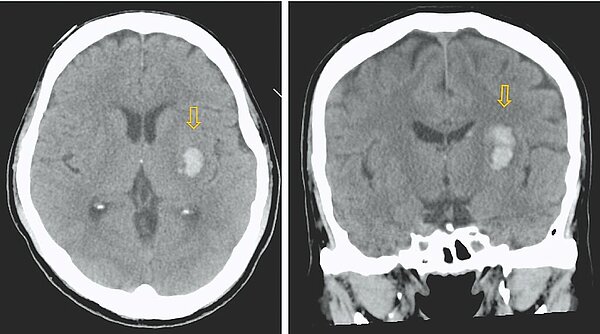

初三氣溫驟降,容易引發血管收縮,急診出現不少急性腦中風、心肌梗塞病人,土城長庚醫院急診醫學科主任醫師薛承君表示,若民眾出現臉歪嘴斜、單側手腳無力、講話不清楚三項症狀之一,很可能是發生急性腦中風,須立即送醫。

薛承君指出,高齡及患有高血壓、高血糖、高血脂的三高慢性疾病病人,併發血管硬化的機率較高,若遇寒流來襲,病人血管收縮、容易誘發血管堵塞,造成急性腦中風或急性冠心症,大腦及心肌細胞的壞死程度會隨時間流失漸趨嚴重,造成不可逆之損傷。

薛承君強調,若是梗塞性腦中風,須在3小時內考慮施打血栓溶解劑,有機會降低病人神經學後遺症;急性冠心症病人則需考慮進行緊急心導管,避免突發性心跳停止。